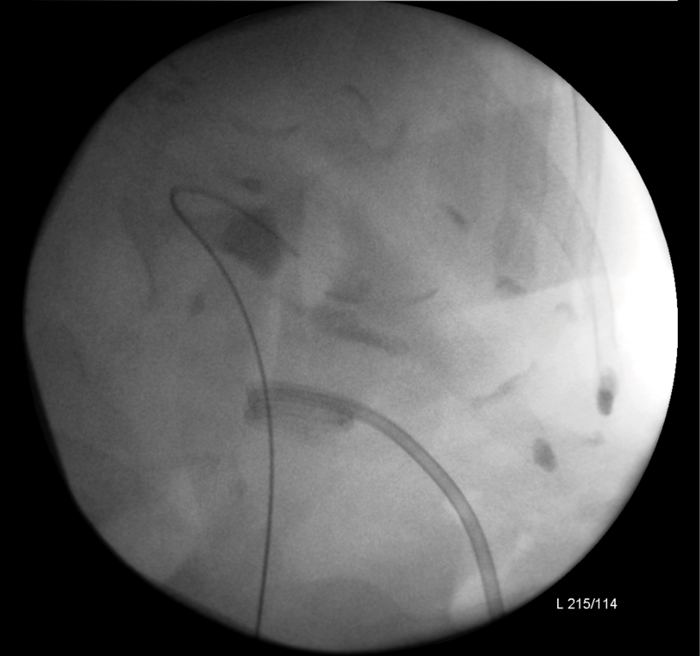

An 80-year-old woman presented with urosepsis requiring direct admission to intensive care. A CT scan demonstrated gas in the collecting system and a nephrostomy was inserted.

Figure 1: CT demonstrating gas in the collecting system.

Figure 2: Nephrostogram showing stone in left kidney with nephrostomy in place prior to flexible ureteroscopy.

The patient made a good recovery from her life-threatening sepsis, retaining function on a DMSA scan and underwent a flexible ureteroscopy to clear the stone. Gas forming organisms in the urinary tract result in dramatic imaging but should not distract from the patient’s clinical condition. A conservative approach may avoid a nightmare nephrectomy in a highly morbid patient.